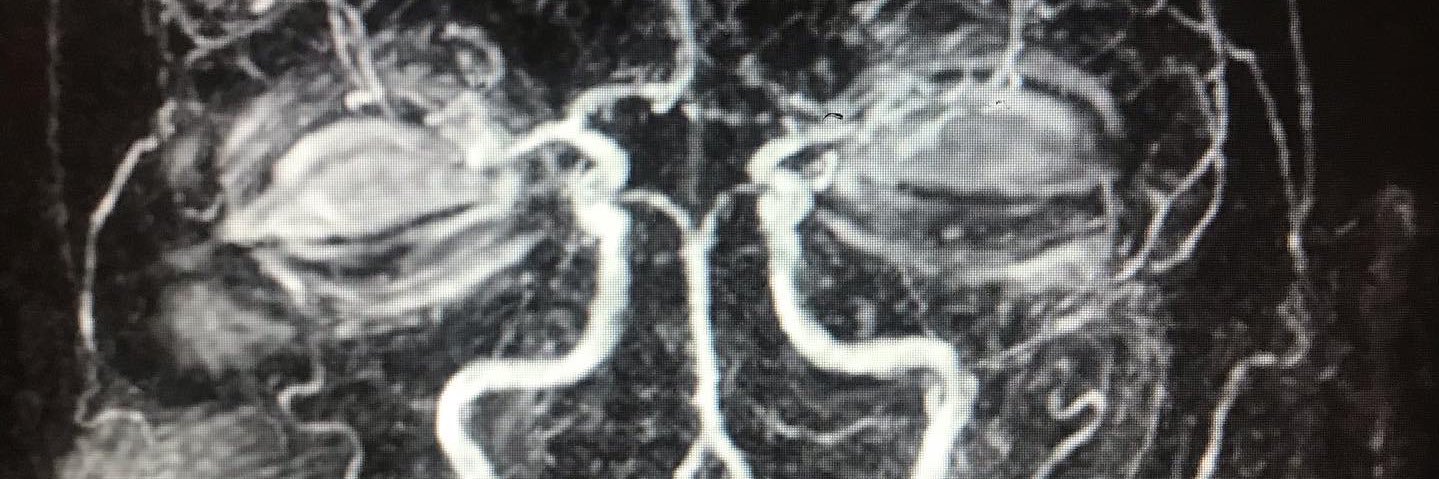

doi.org/10.1111/ncn3.1… challenging diagnosis entity. Check out our recent review in the topic, including great images and a scheme of the cortical veins. @VictorM58763129 @gabeknowz @tuliobueso

@rkchoi Always challenging cases. Wanted to share a recent review we did about this topic, a few good pictures and scheme of the superficial cerebral veins. onlinelibrary.wiley.com/doi/full/10.11… doi.org/10.1111/ncn3.1…